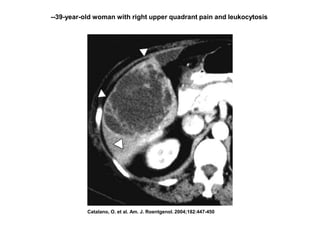

IMAGENOLOGÍA

TAC:

•Método de elección para detectar

lesiones hepáticas

• Visualiza el hígado en su totalidad.

• TAC con técnica helicoidal trifásica

detecta lesiones de 0.5 cm.

• Permite observar abscesos en hígado

graso y tiene una sensibilidad y

especificidad del 95%.

Catalano, O. et al. Am. J. Roentgenol. 2004;182:447-450

--39-year-old woman with right upper quadrant pain and leukocytosis